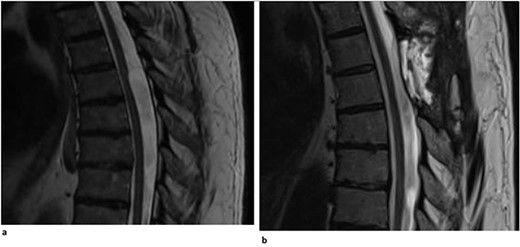

A 67-year-old man presented with a 1-year history of midline back pain that radiated down his right side and myelopathic symptoms. He stated that his symptoms worsened over the last year, and he felt generally weak in the lower extremities, causing problems with ambulation. He did not have any bowel or bladder incontinence, and there was no history of spinal surgery or syrinx expansion. MR imaging demonstrated a spinal cord indentation along the dorsal surface of the spinal cord at the T5 vertebral body level (Fig. 1a). It was hypothesized that the appearance of the spinal cord indentation was secondary to an arachnoid web. The patient underwent T5-T6 laminectomies for intradural exploration for arachnoid web resection at the level of the spinal cord narrowing. The arachnoid web was inspected, and the area of tether was identified and removed using microsurgical tools and technique (Video S1). Postoperatively, the patient reported improvement in back pain, increased strength within the lower extremities, and mild chest wall numbness. Follow-up MR imaging demonstrated resolution of the dorsal indentation and cord expansion (Fig. 1b).

(a) Dorsal indentation (scalpel sign) demonstrated in thoracic spine preoperatively (Patient A). (b) Postlaminectomy and resection of posterior arachnoid web demonstrating resolution of dorsal indentation and cord signal changes (Patient A).